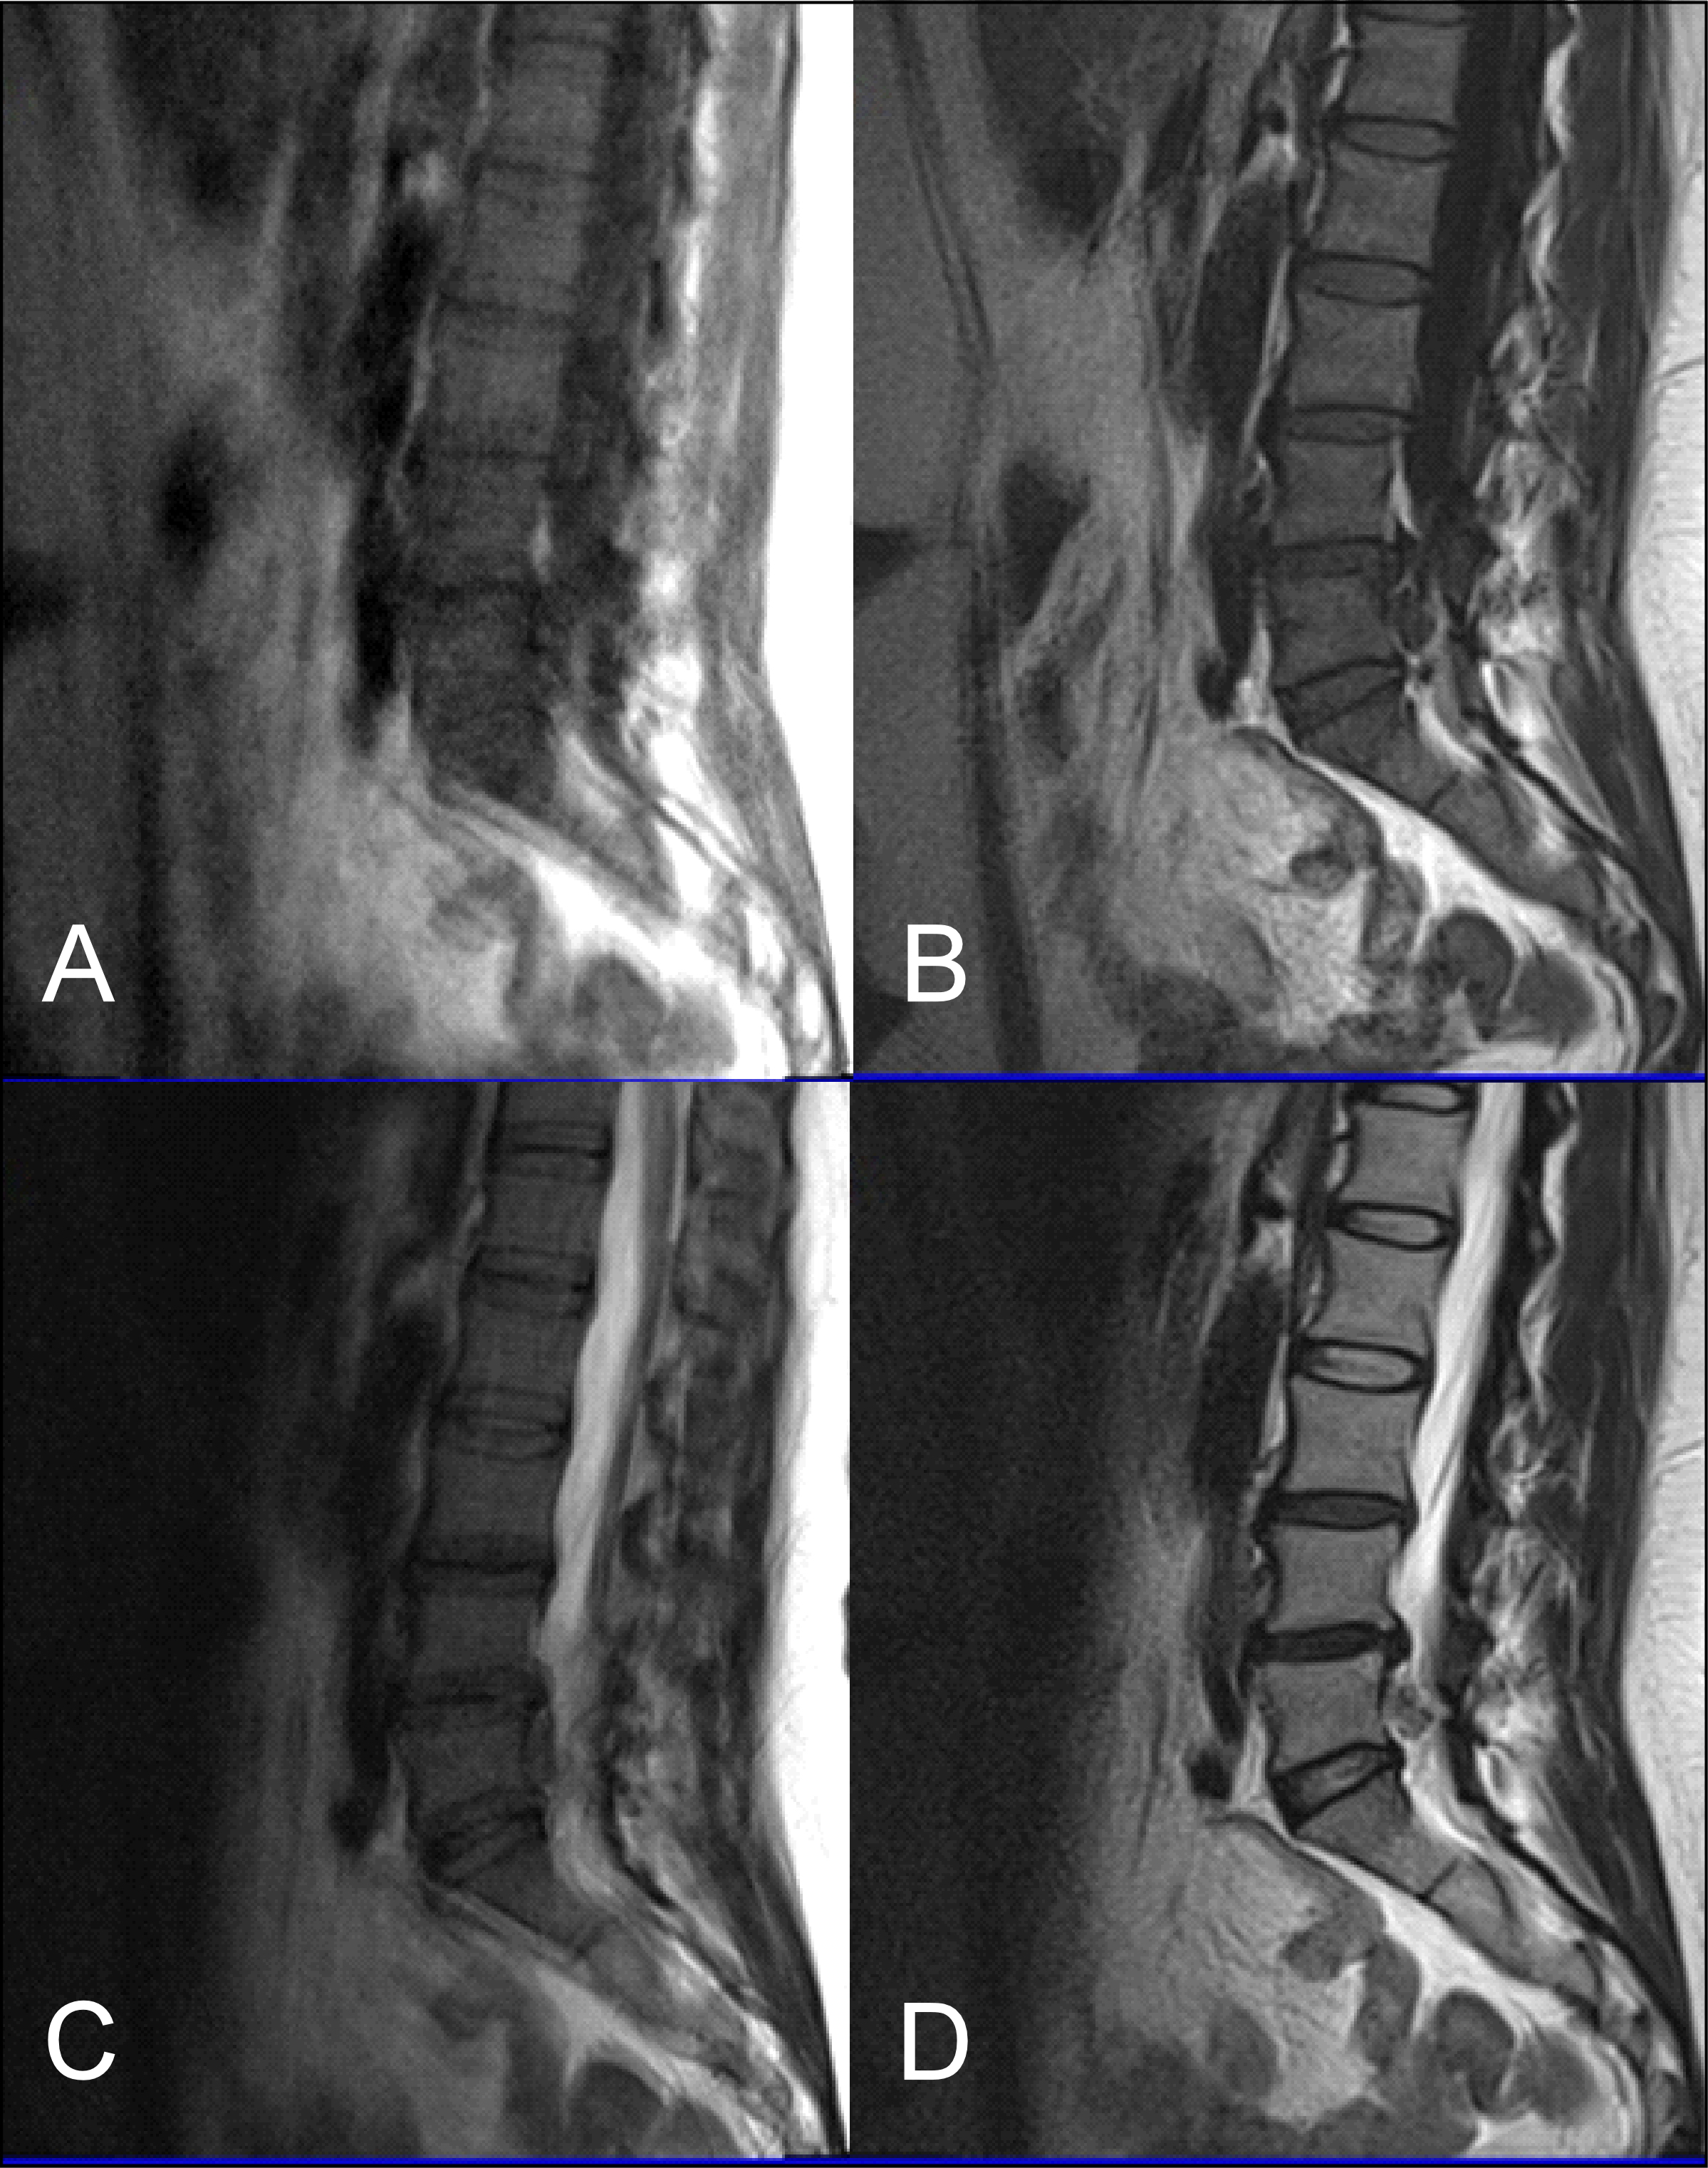

The results obtained from the quantitative analysis of this study showed that the SNR and CNR results were significantly greater for T1W-FLAIR BLADE. More specifically, T1W-FLAIR BLADE sequence achieved better CSF nulling and better contrast between spongy bone and intervertebral disc as well as between spongy bone and intervertebral disc with CSF (Figure 2). A study by Alibek et al., has also demonstrated the superiority in image contrast of T1W-FLAIR images showing that they achieve better lesion to background and grey to white matter CNR [19]. The inherent restrictions of parallel imaging, i.e., reduction of SNR and increased possibility for reconstruction artifacts, were confirmed in our findings where the images without parallel imaging had better SNR (Figure 3).

As stated earlier, sagittal T1 weighted images play an integral role in the MR imaging of the L-spine. One of the reasons is that they provide great information about anatomical structures. In order to assess the importance of the BLADE sequence compared to a TSE, both a qualitative and quantitative analysis were performed by evaluating contrast in between anatomical structures and the SNR, CNR and ReCon measurement respectively [18]. Although T1W-TSE is a faster sequence, T1W-FLAIR BLADE scored better in quantitative and qualitative analyses. Pathologies and abnormalities were better visualized in the latter one. Furthermore, in T1W-FLAIR BLADE there was improved image contrast as well as greater depiction of anatomical structures and either degeneration or metastatic lesions. Both the quantitative and qualitative analysis showed that T1W-FLAIR BLADE achieved better results than T1W-TSE. In addition to that, T1W-FLAIR BLADE images without parallel imaging were found to have better quality than the T1W-FLAIR BLADE images with parallel imaging. Although they both eliminated motion artifacts, the images without parallel imaging have better SNR as well as better contrast between tissues (Figure 3). Moreover, a study showed that T1W-FLAIR images can successfully eliminate chemical shift artifacts compared to T1W-TSE due to greater receiver bandwidth [8]. This statement was confirmed by our findings (Figure 4).